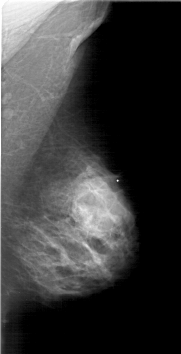

A_1803_1.LEFT_MLO

LEFT_MLO LINES 5941 PIXELS_PER_LINE 3436 BITS_PER_PIXEL 12 RESOLUTION 43.5 OVERLAY